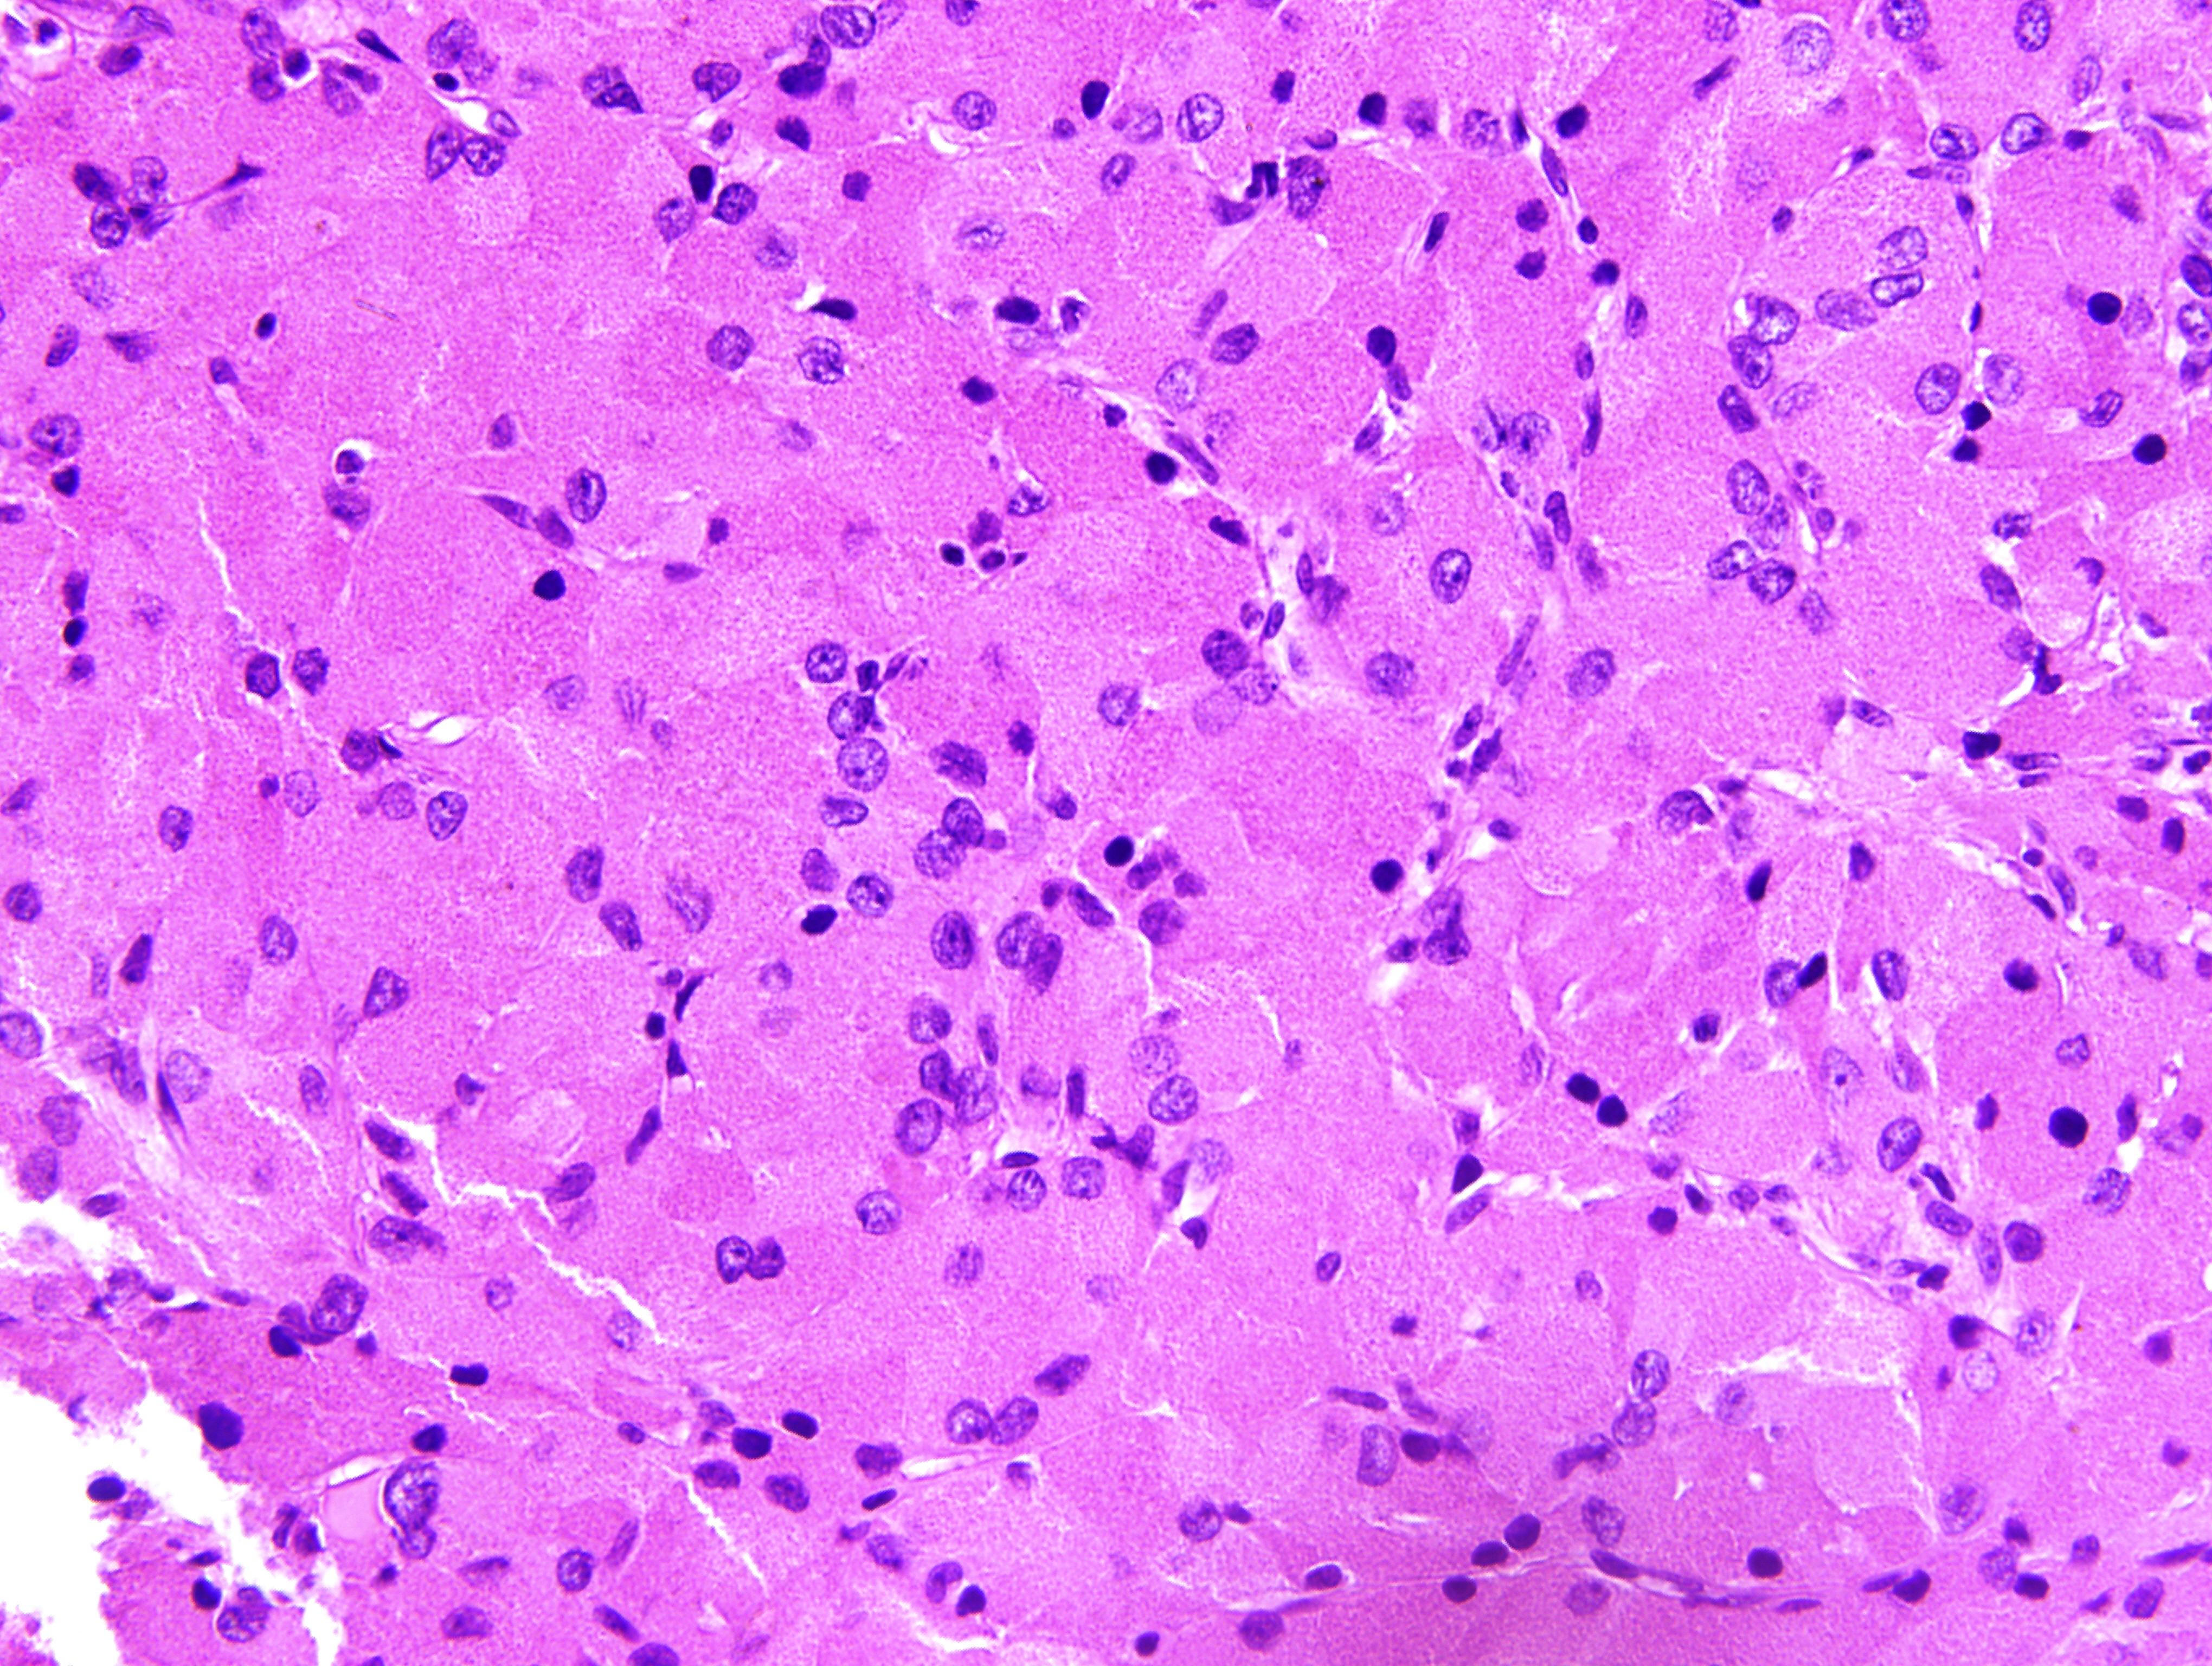

| 4. | Descripción | Resumen | Introducción. Es un tumor benigno muy infrecuente, supraselar y/o intraselar, que se origina en la neurohipófisis o en el infundíbulo. Se presenta habitualmente en la edad adulta, con mayor incidencia en mujeres. No existen síntomas o signos específicos que permitan distinguirlo de otras lesiones supraselares, aunque la diabetes insípida es relativamente infrecuente. El diagnostico final es generalmente a través de la anatomía patológica donde se constatan células con citoplasma granular eosinófilo, debido a la presencia de abundantes lisosomas. Estos tumores son immunonegativos para todas las hormonas de la hipófisis anterior, de variable positividad para la proteína S-100, y por lo general negativos para la proteína gliofibrilar ácida (GFAP). La resonancia magnética suele mostrar una lesión supraselar bien circunscrita, con captación homogénea o heterogénea de contraste. La cirugía es el tratamiento de elección. Objetivo. Dar a conocer la presencia de este tumor en nuestro medio. Material y método. Paciente de femenina de 48 años de edad, que ingresa por alteraciones del campo visual (hemianopsia bitemporal) y cefalea holocraneal.En el examen físico se constata papiledema bilateral. Resultado y discusión. Se concluye el caso como un tumor de células granulares de la neurohipofisis, y se compara con el reportado en la literatura. |

Cd 68 (27KB) laminas histologica proteina acida gliofibrilar ( GFAP ) (4MB) hematoxilina y eosina (5MB) S-100 (6MB) RMN de hipofisis (62KB) |